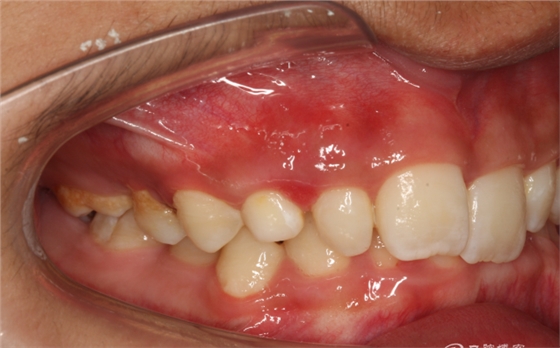

圖3.左側(cè)位咬合影像